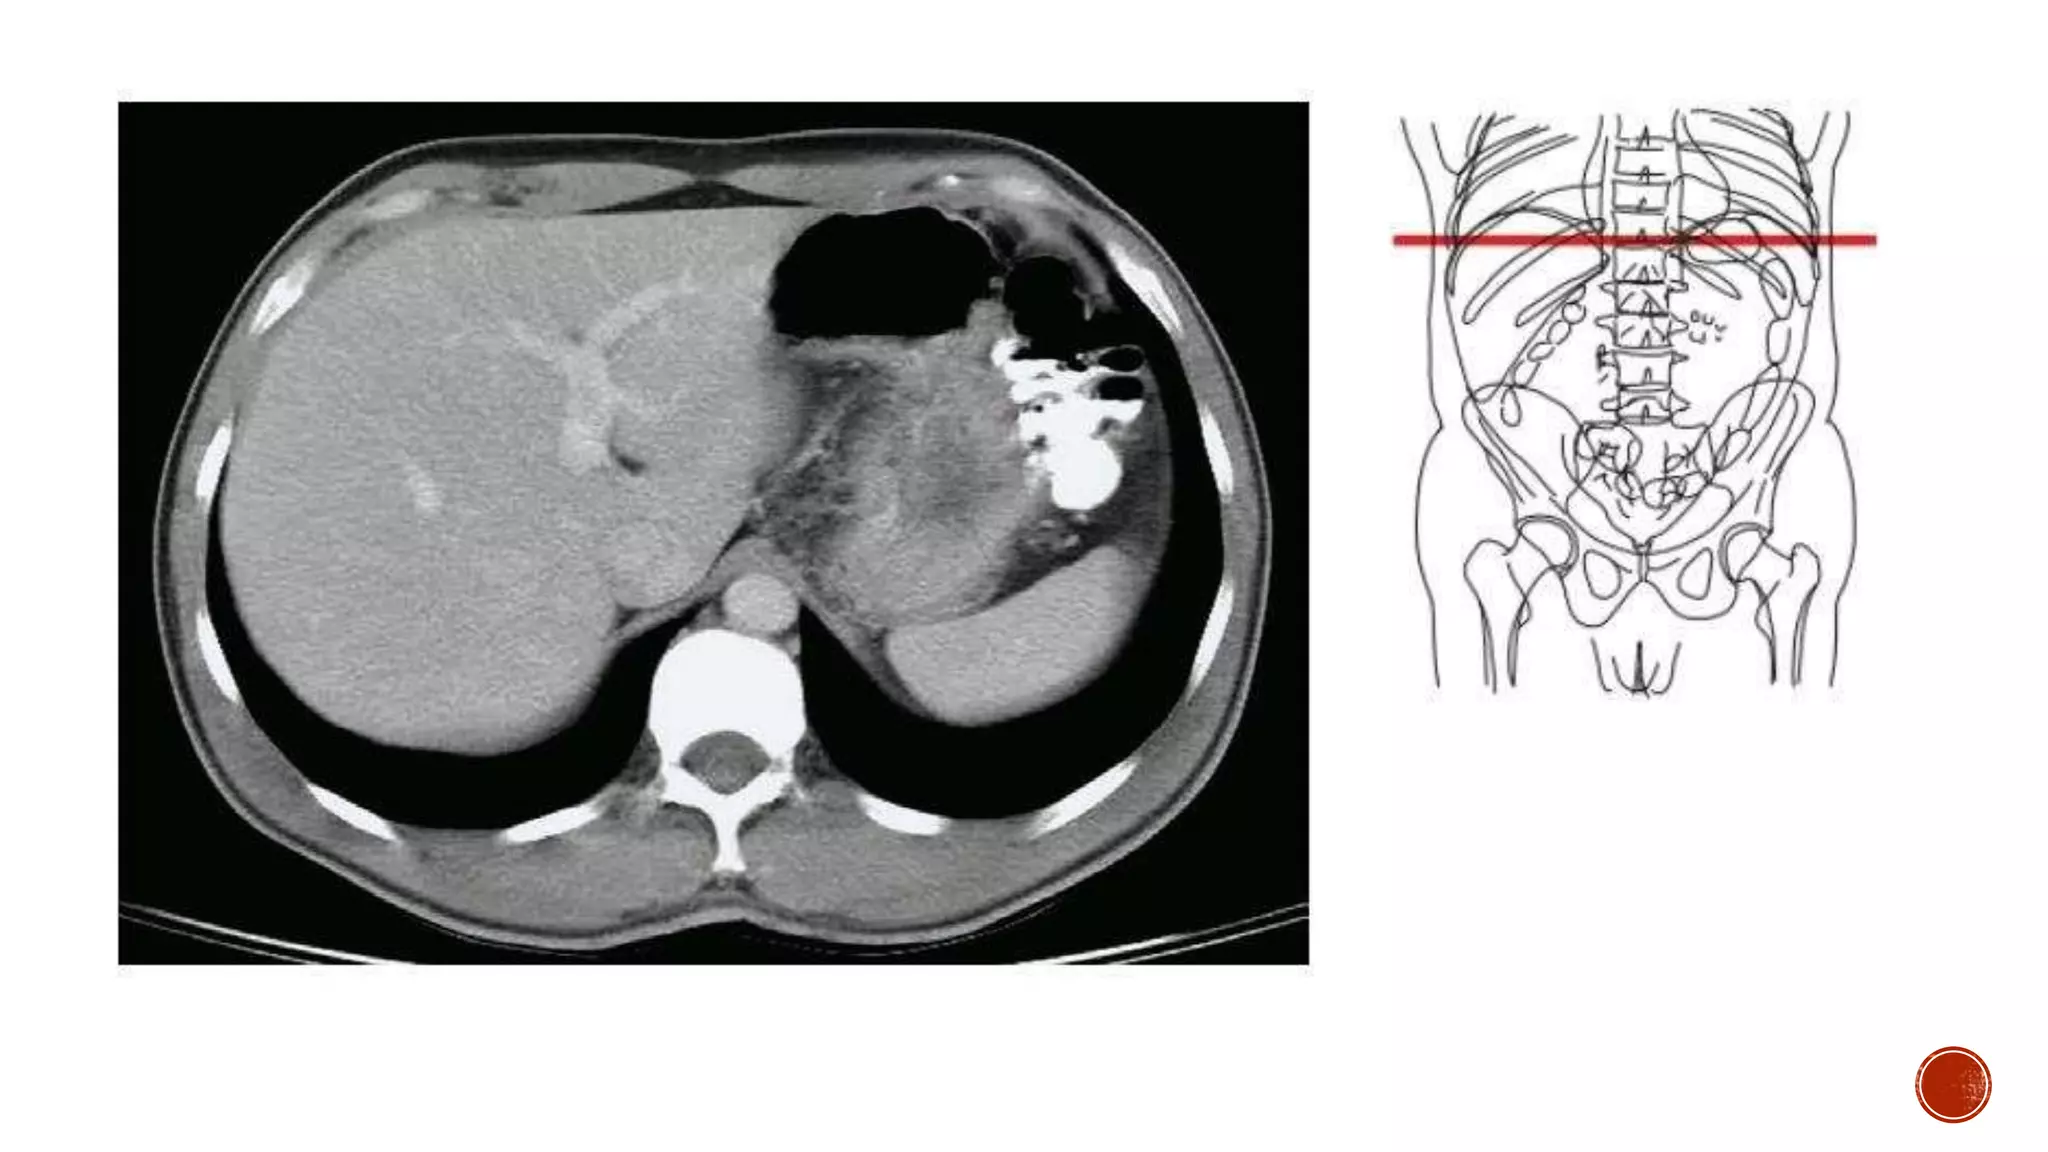

The document describes the anatomy of the abdomen and pelvis region of the human body. It lists over 40 structures and their locations, including major organs like the liver, kidneys, intestines, blood vessels and muscles of the abdominal wall and pelvis. The structures are grouped into sections focusing on different anatomical areas like the abdomen, retroperitoneum, pelvis and gluteal region.